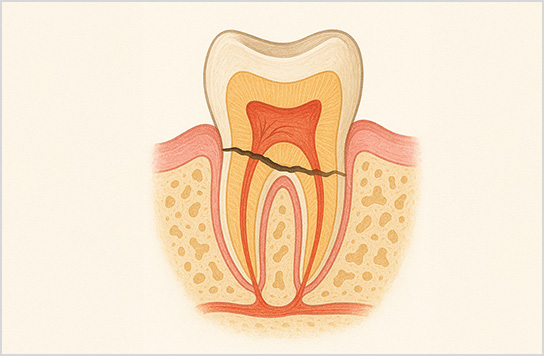

他院で歯が割れているので抜

歯と言われた場合でも、

割れていないケースも多くあり、

その場合は歯を残せます。

■破折歯

他院で歯が割れているため抜歯と言われたケース。当院で診断したところ破折ではないことが判明し、適切な処置で抜歯せず歯を再生させた。